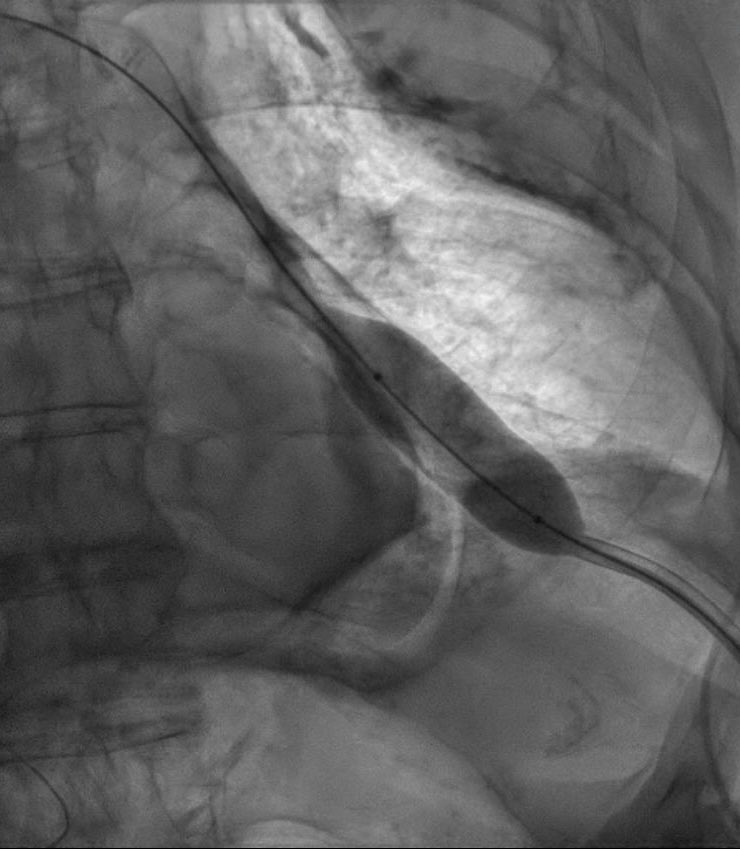

La pericardiotomia con balón es una alternativa a la ventana pericárdica quirúrgica en pacientes con derrame recidivante.